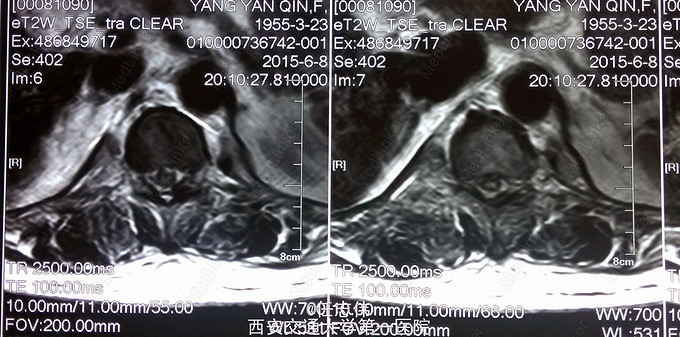

患者女性,60岁,车祸伤致双下肢感觉活动不能8h入院。 8小时前坐农用车时,被横杆撞倒腰部,摔下后感觉胸背部疼痛,双下肢活动不能,伴有短暂昏迷病史。遂来我院就诊。

左侧胸壁广泛压痛,呼吸急促。专科查体:胸背部广泛压痛,自腹股沟平面以下感觉、运动消失,腹壁反射消失,肛门反射消失,巴氏征阴性。双上肢感觉运动正常,骨盆分离挤压试验阴性。

诊断:1.胸11椎体骨折伴截瘫(Frankel A级)2.闭合性胸部损伤,肺挫伤,多发肋骨骨折,双侧胸腔积液 处理:1.急诊入院告病危,心电血氧监护;2.予以甲强龙冲击治疗;3.次日复查胸部CT,查看肺部损伤情况及胸腔积液,后予以右侧放置闭式引流。患者氧合不稳定,2日后复查胸片胸腔积液减少,予以行后路减压内固定融合术。 手术:术中见局部软组织损伤严重,胸11-12棘上、棘间韧带断裂,胸10、11、12双侧关节突有骨折移位,胸11椎板骨折,胸11左侧不能置入椎弓根螺钉,遂行单纯固定。脊髓局部挫伤明显,并有硬膜破损,予以处理。